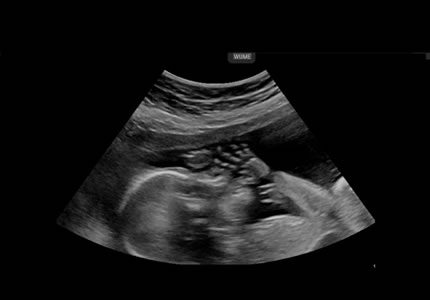

Gender & Mid-Pregnancy Scans (16 – 24 Weeks)

- Discover the sex of your baby with high-resolution imaging. While the reveal is the highlight, our sonographers always perform a professional wellbeing check, monitoring growth and heart activity, to ensure your baby is hitting their milestones.

- £69

- A thorough "top-to-toe" structural survey of your baby. We systematically evaluate the anatomy—including the brain, spine, heart, and limbs—to screen for developmental markers. This scan offers an in-depth look at your baby's progress during the halfway point of your pregnancy.

- £199